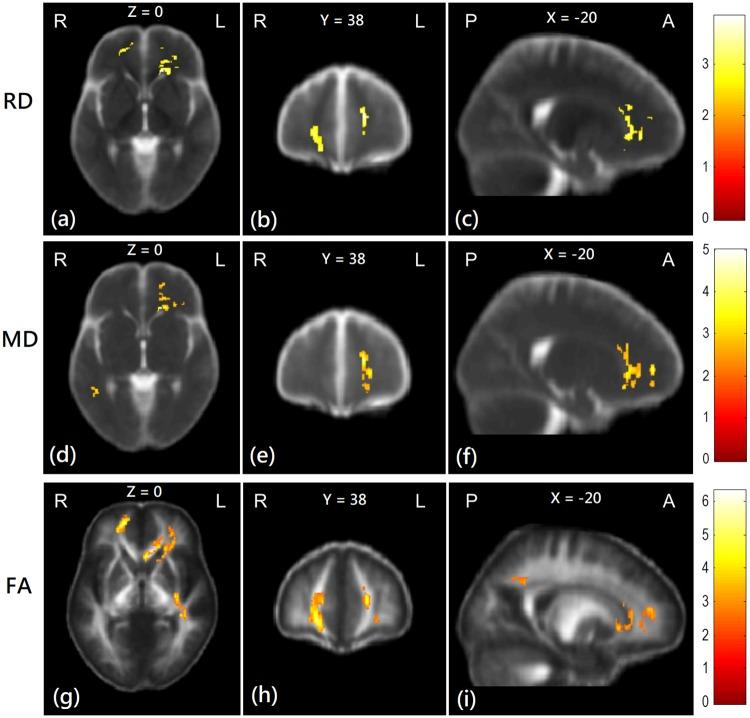

In the ESRD patients, diffusivity indices were significantly increased and the fractional anisotropy was significantly decreased in both scans, as compared with healthy controls. Longitudinal comparisons showed significant white-matter alterations in healthy controls in three years, but little or no significant alterations were noted in the ESRD patients after additional 3-year hemodialysis.

与健康对照组相比,ESRD 患者在两次扫描中,弥散指数均显著升高,各向异性分数显著降低。纵向比较显示,健康对照组在三年内有明显的脑白质改变,但在 ESRD 患者在额外的 3 年血液透析后,几乎没有或没有明显的改变。